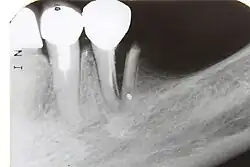

Im Verlauf einer odontogenen Infektion stirbt unbehandelt die Pulpa ab und die Keime breiten sich im System der Wurzelkanäle aus. Der Körper reagiert mit einer Entzündung des Zahnhalteapparates (Parodontitis apicalis) im Sinne einer Abwehrreaktion. Eine Parodontitis apicalis kann in einer akuten oder einer chronischen Form vorliegen. Die akute Form ist oft mit Schmerzen verbunden, sie kann unter Umständen röntgenologisch nur schwer verifiziert werden, während eine chronische Parodontitis apicalis bei einer Auflösung der Knochenstruktur im Bereich der Wurzelspitze im Röntgenbild als Aufhellung sichtbar sein kann. Im Röntgenbild erscheint die Aufhellung dunkel, da das Röntgenbild ein Negativ darstellt.

Nach einer Lokalanästhesie erfolgt die Längenbestimmung des Wurzelkanals oder der -kanäle (anhand eines Röntgeneinzelbilds in Verbindung mit speziellen Messnadeln oder auf elektrischem Weg durch Endometrie). Anschließend werden die Kanäle mit Handfeilen oder maschinell angetriebenen rotierenden Instrumenten konisch erweitert („aufbereitet“). Durch Spülungen mit verschiedenen Lösungen, wie z. B. NaOCl, 3-prozentige H2O2-Lösung, EDTA oder CHX, werden Verunreinigungen aus den Kanälen entfernt, die Schmierschicht beseitigt und Mikroorganismen bekämpft. Mittels Laser kann vor der Abfüllung der Kanäle zusätzlich zu den üblich verwendeten Spüllösungen eine Desinfektion erfolgen. Die Spüllösungen können durch Ultraschall aktiviert werden, um die Wirkung zu verstärken. Auf diese Weise können auch Kanalverzweigungen und infizierte Dentinbereiche desinfiziert werden, die einer instrumentellen Aufbereitung nicht zugänglich sind. Auf Endodontie spezialisierte Zahnärzte verwenden bei der Wurzelkanalbehandlung ein Operationsmikroskop, das mit seiner zusätzlichen Lichtquelle mit koaxialem Licht und der Vergrößerung das Auffinden und Betrachten der Kanaleingänge erleichtert.

Der Ablauf einer Wurzelkanalbehandlung am Zahn 17

-

Röntgenaufnahme vor Wurzelkanalbehandlung -

Zahn eröffnet, Pulpa soll entfernt werden -

Pulpa exstirpiert -

Messaufnahme -

Drei Kanäle aufbereitet und ausgeformt -

Oft haben obere Molaren allerdings vier Kanäle -

Alle vier Kanäle abgefüllt -

Kontrollaufnahme nach Wurzelkanalbehandlung -

Deckfüllung -

Kontrollaufnahme nach 20 Monaten